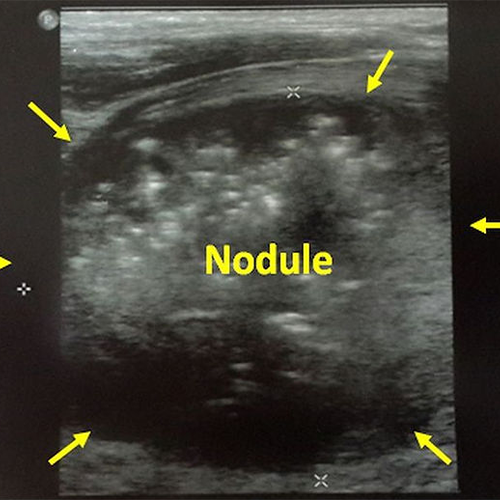

In our 32 year-old male patient with a 62x50x47 mm semisolid nodule in the right thyroid lobe, ultrasound-guided alcohol ablation were done 2 times with 3 months interval. One year after the first ablation, a 90% volume reduction was seen on ultrasound.